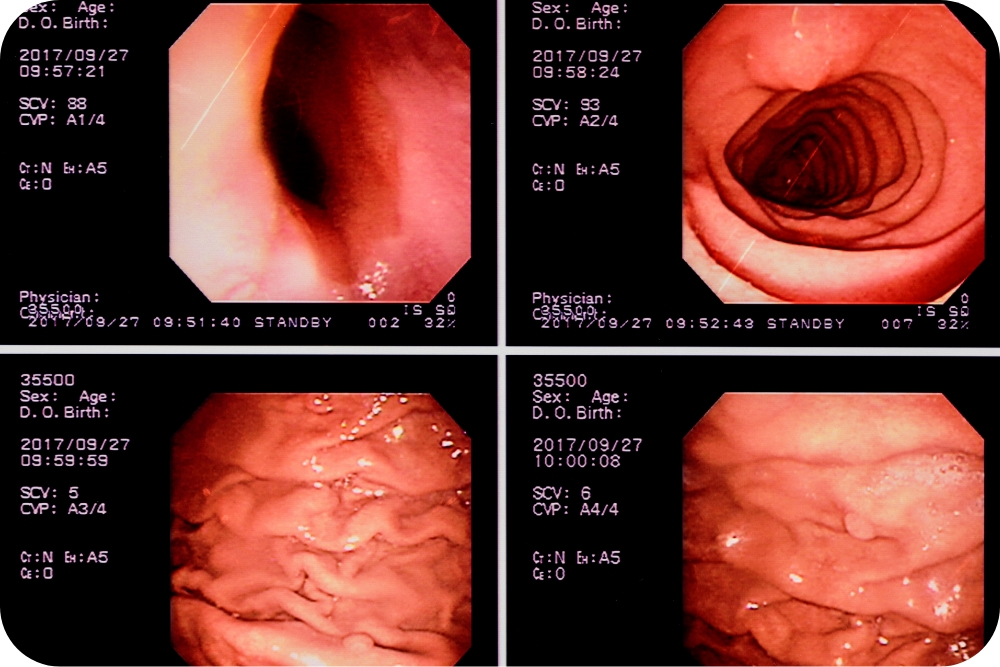

高性能な大腸カメラを導入

当院で使われる高性能な大腸カメラでは、約100倍の高解像度の拡大画像を取得られたり、BLI(狭帯域光観察)という特殊な光を使用してわずかな構造や色の違いを確認できたり、また、LCIという明るい光で病気の部分を見逃さないようにすることができます。

大腸カメラ後は、はっきりと目覚めるまで30分~1時間ほどベッドでお休みいただいた後に、検査画像を見ながら医師が結果の説明をします。検査で組織を採取したり、ポリープを切除した場合は、その病理検査の結果が出るまで約2週間の時間をいただいております。